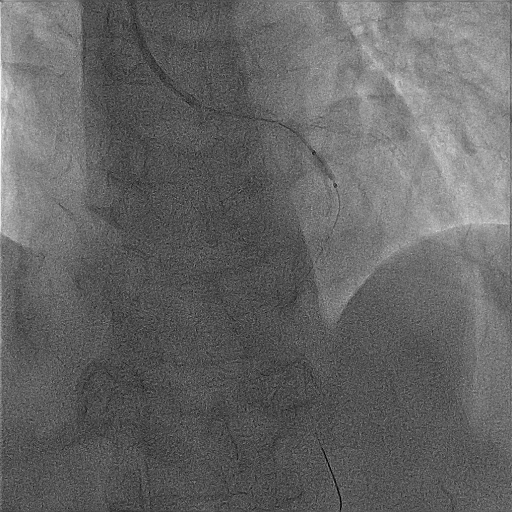

手术前冠脉造影提示,左主干至前降支中段钙化明显,前降支近段起弥漫性病变,严重处80%狭窄。

术前造影指示左主干至前降支中段钙化明显